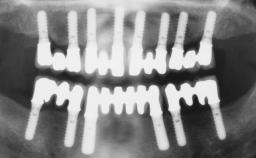

Immediate Loading of Six Implants in the Mandible and Six Implants in the Maxilla and Final Restoration with Full-Arch CAD/CAM Metal Framework FDPs Involving Digital Planning and Guided Surgery

Ali Tahmaseb, Renaat De Clerck, Daniel Wismeijer

Immediate loading of dental implants is increasingly popular with clinicians and patients. The idea of delivering a restoration directly after implant insertion,combined with a less invasive procedure (flapless protocol), has made treatment protocols involving dental implants more accessible to dentists and patients. However,immediate-loading concepts require sophisticated and exact planning. To facilitate this, conventional panoramic tomographs and periapical radiographs are often taken with the patient wearing a radiographic template simulating the preoperative prosthetic design. However, these radiographs do not provide all the necessary information. In addition, some protocols call for conventional surgical templates fabricated on the diagnostic cast. These will inform the bone drilling points and drill angles, but do not reference the underlying anatomical structures or provide exact 3-D guidance.

# of Implants 12